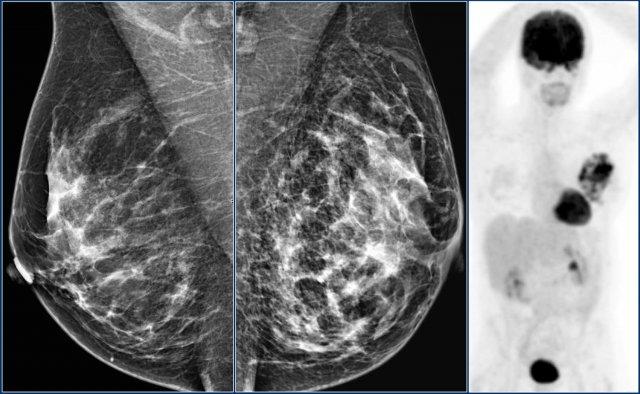

Trong phiên bản BI-RADS 2003, việc phân loại thành phần tuyến vú dựa trên mật độ tổng thể, chia thành các nhóm ACR: nhóm 1 (<25% mô tuyến xơ), nhóm 2 (25-50%), nhóm 3 (50-75%) và nhóm 4 (>75%).

Trong BI-RADS 2013, việc sử dụng tỷ lệ phần trăm không được khuyến khích, vì trong từng trường hợp cụ thể, điều quan trọng hơn là đánh giá khả năng một khối có thể bị che khuất bởi mô tuyến xơ, thay vì dùng tỷ lệ phần trăm mật độ vú như một chỉ số nguy cơ ung thư vú.

Trong phiên bản BI-RADS 2013, phân loại thành phần tuyến vú được thay đổi thành các nhóm a, b, c và d kèm theo mô tả:

- a– Tuyến vú gần như hoàn toàn là mô mỡ.

Nhũ ảnh có độ nhạy cao trong trường hợp này. - b– Có các vùng mô tuyến xơ rải rác.

Thuật ngữ “mật độ” mô tả mức độ suy giảm tia X của mô vú, không phải các tổn thương nhũ ảnh riêng biệt. - c– Tuyến vú có mật độ không đồng nhất, có thể che khuất các khối nhỏ.

Một số vùng trong tuyến vú có mật độ đủ cao để che khuất các khối nhỏ. -

d

– Tuyến vú có mật độ rất cao, làm giảm độ nhạy của nhũ ảnh.

Lưu ý ở ví dụ bên trái, thành phần tuyến vú được phân loại là c – mật độ không đồng nhất, mặc dù thể tích mô tuyến xơ chiếm dưới 50%.

Mô tuyến xơ ở phần trên có mật độ đủ cao để che khuất các khối nhỏ.

Do đó được phân loại là c, vì các khối nhỏ có thể bị che khuất.

Theo phân loại cũ, trường hợp này sẽ được gọi là ACR 2: mật độ 25-50%.

Ví dụ bên phải có hơn 50% mô tuyến và cũng được phân loại là thành phần c.